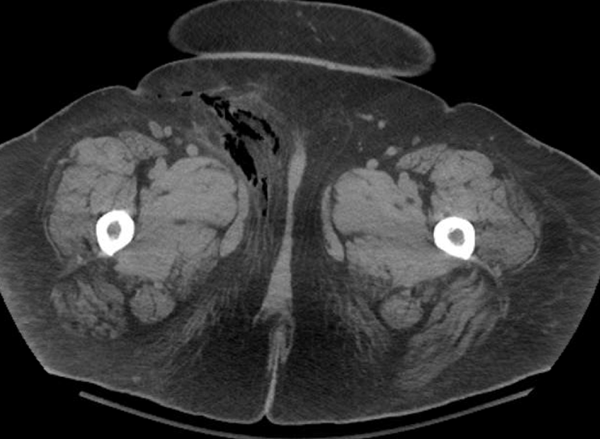

CT abdomen/pelvis without contrast (see Figures 1-3) revealed extensive inflammatory stranding involving the anterior/lateral right pelvic soft tissues with soft tissue gas identified tracking from the lateral right pelvis soft tissues at the level of the iliac crest medially and inferiorly down to the level of the right groin.

The inflammatory stranding reached the anterior rectus fascia without intraperitoneal extension. These findings were concerning for necrotizing fasciitis. The patient was taken emergently to the operating room where she underwent wide excision and debridement of skin, fat, fascia of the right groin and perineum totaling 30 x 15 x 8 cm. She was then transferred to the intensive care unit, intubated, and put on inotropic support.